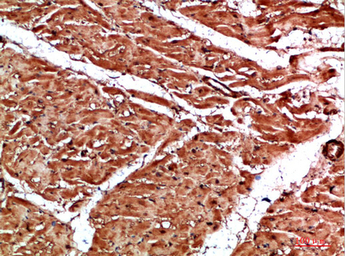

IHC-P analysis of human skeletal muscle tissue using GTX34284 Titin antibody.

Dilution : 1:200